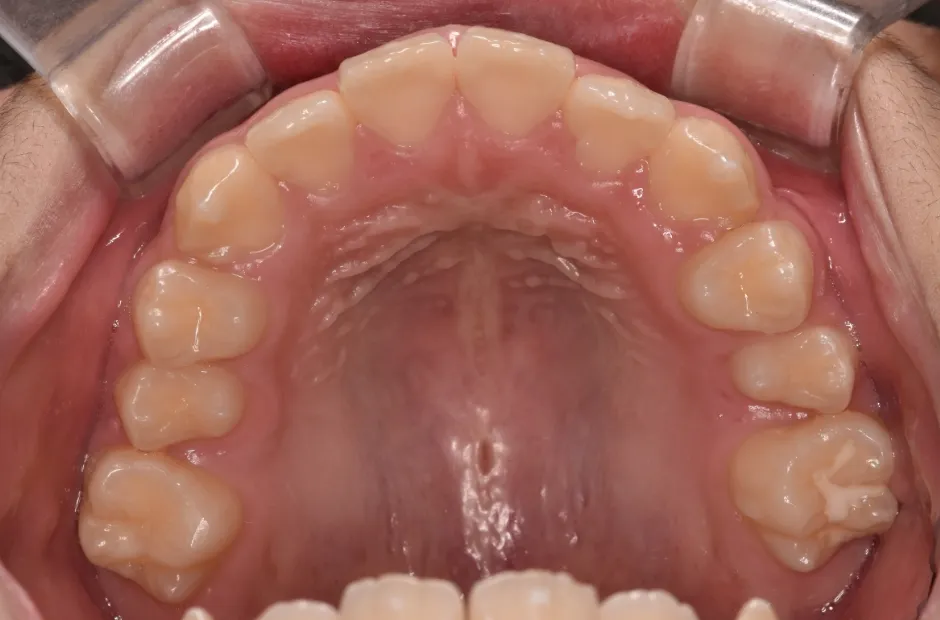

反対咬合

| 診断名・主訴 | 前歯反対咬合 |

|---|---|

| 年齢・性別 | 12歳・男性 |

| 治療期間・回数 | 1年半 18回 |

| 治療に用いた主な装置 | リンガルアーチ(前方誘導弾線) |

| 抜歯部位 | なし |

| 治療費 | 35万円(税抜) |

| リスク・副作用 | 装置による違和感・疼痛・歯肉退縮・歯根吸収・虫歯のリスクなど |

治療前

治療中

治療後